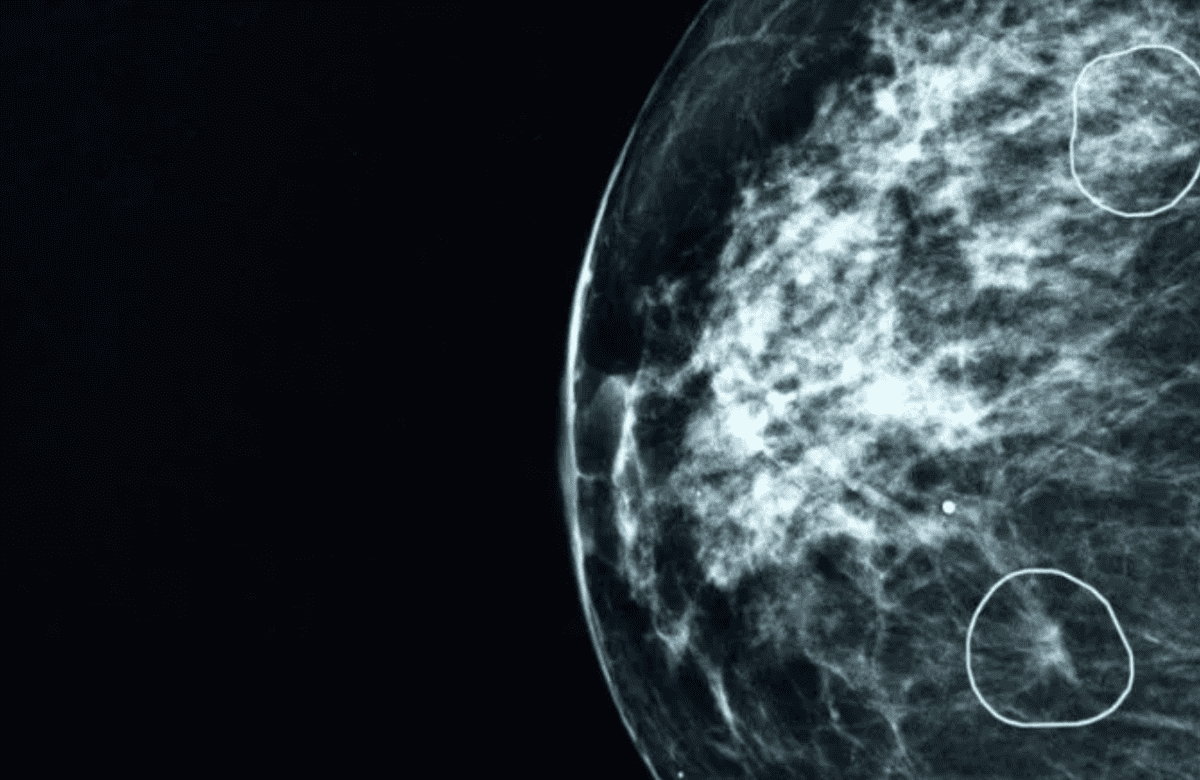

Conozca cómo funciona la herramienta de IA que detecta tumores de cáncer

La herramienta logró detectar tumores que fueron invisibles a los ojos de los médicos.